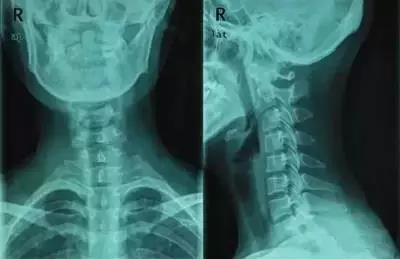

王先生是一位长期伏案工作者,长期的工作姿势使得他得了颈椎病。在我院诊治的过程中,我的同事叮嘱王先生,平时要多仰头,伏案工作时间不要超过1个小时,晚上睡觉可以枕空酒瓶或者圆形颈椎枕。旁边的李大妈听到了也回家效仿。一个疗程不到,王先生的症状缓解了很多,但李大妈缺越来越不适,甚至落枕了。

枕空酒瓶的目的在于恢复颈椎生理曲度,并不是治疗颈椎病。要想枕空酒瓶或者圆形颈椎枕,这是需要符合几个条件的:

第一,颈项部的不适,主要是由于颈椎生理曲度变直引起的。并且没有较为严重的颈椎生理结构改变。正常情况下,颈椎有一个前凸的弧度,被称为生理性前凸。人们在清醒的情况下,无论是工作还是学习,无论站立、走路还是坐位姿势,都以保持这种自然姿势为最舒服。长时间过度低头,颈后部会感到疲劳。

第二,炎症水肿期是绝对不能枕空酒瓶的。空酒瓶较为坚硬,对项韧带等都是一个不良刺激,容易加重局部水肿。即便有毛巾缠裹,在颈椎没有得到很好放松前提下,突然改变颈椎曲度,一样会加重症状。

第三,酒瓶的直径,需要和人体颈椎生理曲度协调。酒瓶的直径以在睡眠中使颈椎保持正常的生理性前凸最为恰当。这样可使颈部的肌肉、椎间盘、韧带等均处于自然放松的休息状态。

然而对于急性期的患者,由于颈项部软组织水肿炎症,空酒瓶使用不当会加重症状。同时,对于脊髓型颈椎病的患者,更不能随意使用这个方法。还可能因为过度限制颈椎的体位而导致颈部肌肉痉挛,加重病情。

所以,相对于空酒瓶,选择合适的枕头更适合我们。一般来说,单人枕头的长度以超过自己的双肩宽度15厘米为宜。对于习惯仰卧的人来说,其枕头高度应以压缩后与自己的拳头高(握拳虎口向上的高度为拳高标准)相等为宜;而习惯侧睡的人,其枕头高度应以压缩后与自己的一侧肩宽高度一致为宜。